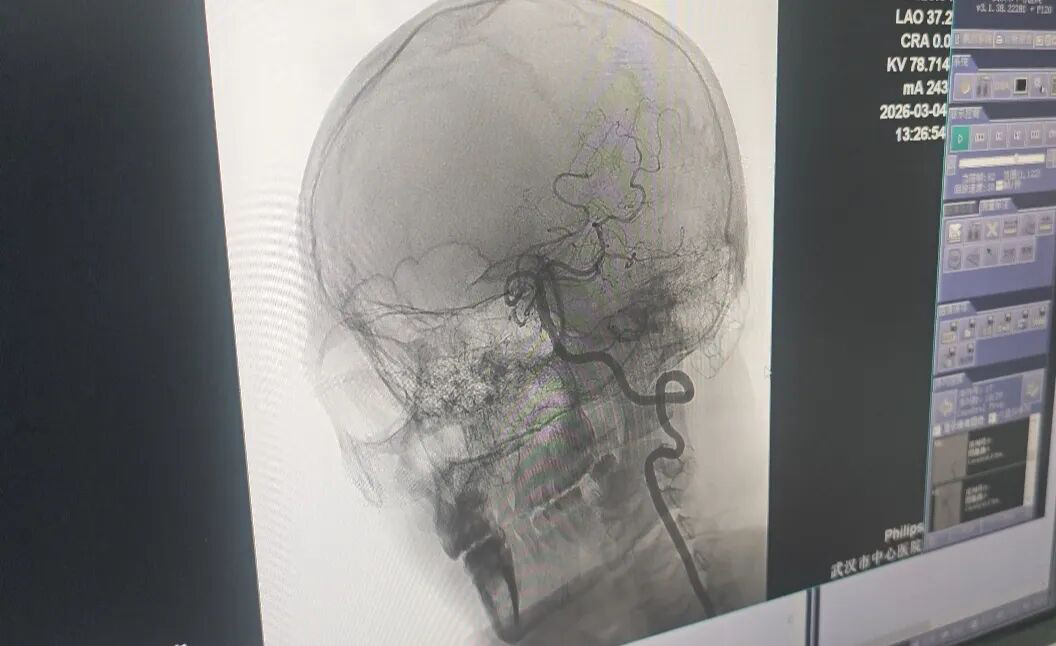

The medical team successfully intervened and revascularized Mr. Wang's blocked blood vessel. *Photo: Li Huizi*

At the hospital, neurologists diagnosed the patient with acute large vessel occlusion and prescribed intravenous thrombolytic medication. However, just 30 minutes later, Mr. Wang's condition worsened. He fell into a deep coma, his left pupil dilated, he lost his light reflex, and experienced complete left-sided paralysis, including facial and tongue paralysis, along with aphasia. Doctors performed an angiogram, revealing a tear in the intimal layer of his vertebral artery. This caused severe hemodynamic disturbance and formed a blood clot that blocked the vessel. Dr. Hung Vi, head of the Neurology Department, explained that the tissue exposed from the damaged intima rapidly stimulated thrombosis, leading to a complete blockage of blood flow.

The emergency team immediately transferred the patient to the interventional cardiology suite. Recognizing that the vertebral artery was not yet completely occluded, specialists decided to perform additional arterial thrombolysis. This combined approach precisely restored blood flow, saving the patient's life.